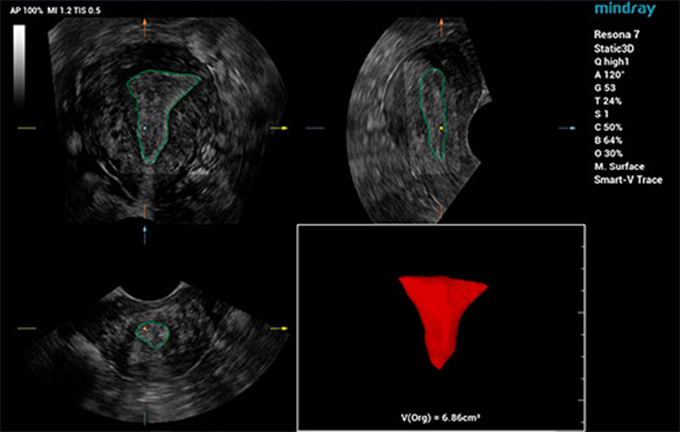

为提升妇产超声检查的效率与准确率,更好地实现生殖系统疾病和肿瘤的早发现,针对卵泡和子宫的超声检查,仁合提出了一系列智能化解决方案,助力医生进行高效临床诊断。比如,面向子宫应用场景,仁合推出了业内首款全自动子宫内膜容受度分析工具Smart ERA,即便针对不同类型的子宫内膜结构,也能够实现3D自动容积成像,并支持子宫内膜体积和厚度以及子宫内膜血流指数的自动测量。精简操作流程,极大地提升了检查一致性与诊断效率,让医生更自信、从容地应对孕前超声检查,如百步穿杨,既快且准。